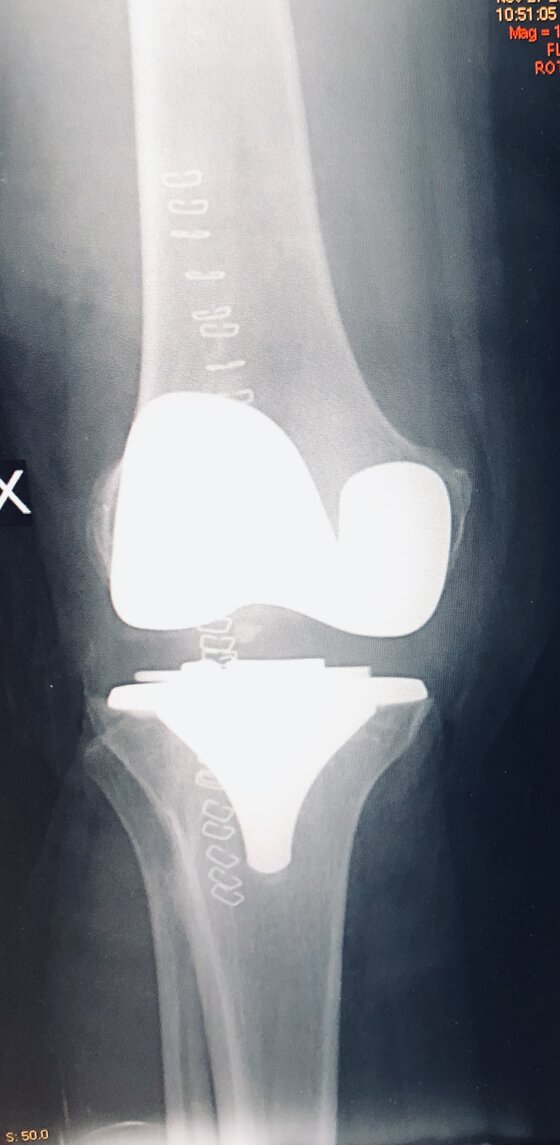

Radiografie post-operatorie in AP e LL di intervento chirurgico di artroprotesi cementata di ginocchio in pz donna con sovrappeso. In questo caso è stata utilizzata una protesi postero-stabilizzata (PS) con sacrificio quindi del legamento crociato posteriore (LCP)